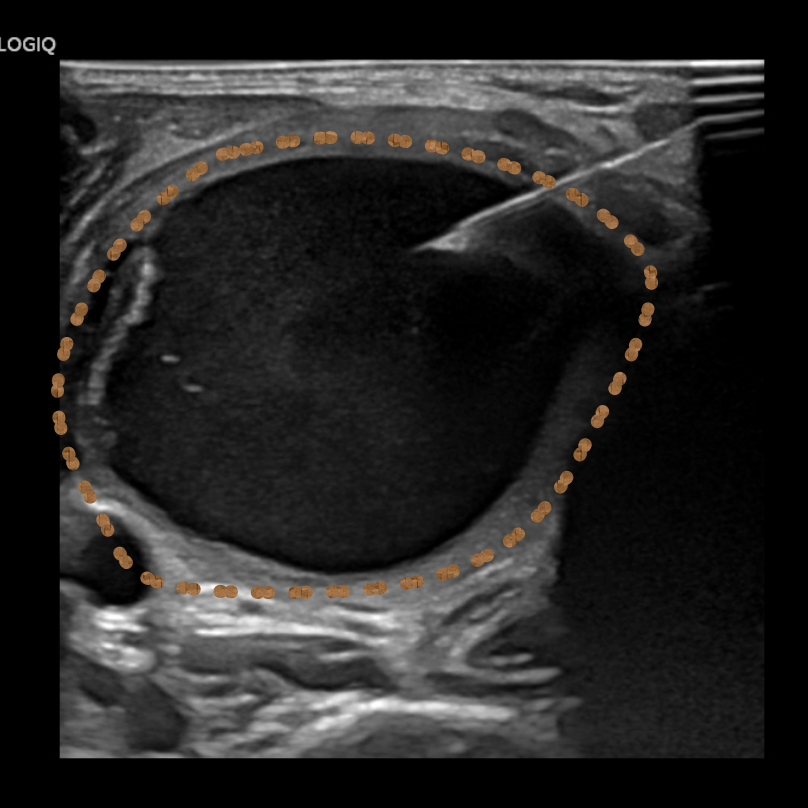

图片

▲王晓明和张轶亮医师为患者行超声引导下肾囊肿穿刺抽液硬化治疗